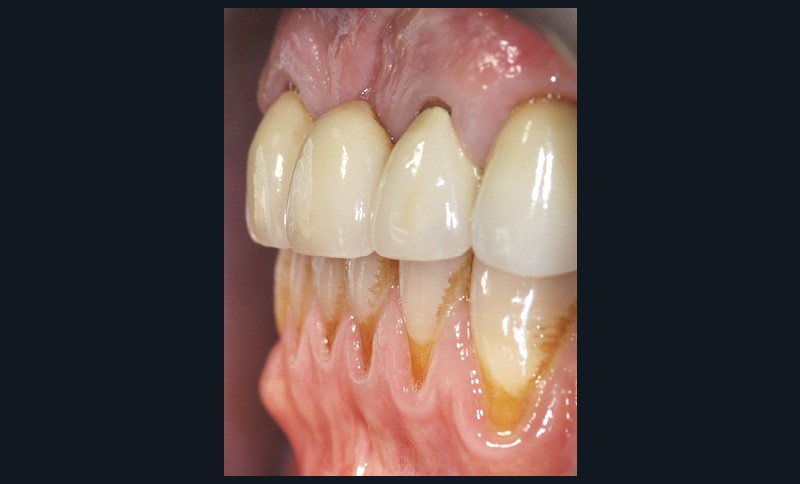

Il débute par l’évaluation des paramètres gingivaux (ligne du sourire [2], biotype parodontal [3], présence ou absence de papilles interdentaires, alignement des collets…). Les paramètres dentaires (origine de l’édentement, état de restauration des dents adjacentes, forme des couronnes dentaires…) compléteront cet examen (fig. 1). L’origine de l’édentement ne doit pas être sous-estimée. Graetz et al. [4] ont démontré que les patients avec des antécédents de maladie parodontale avaient une perte osseuse marginale et des profondeurs de poches plus importantes que les patients avec un parodonte sain.